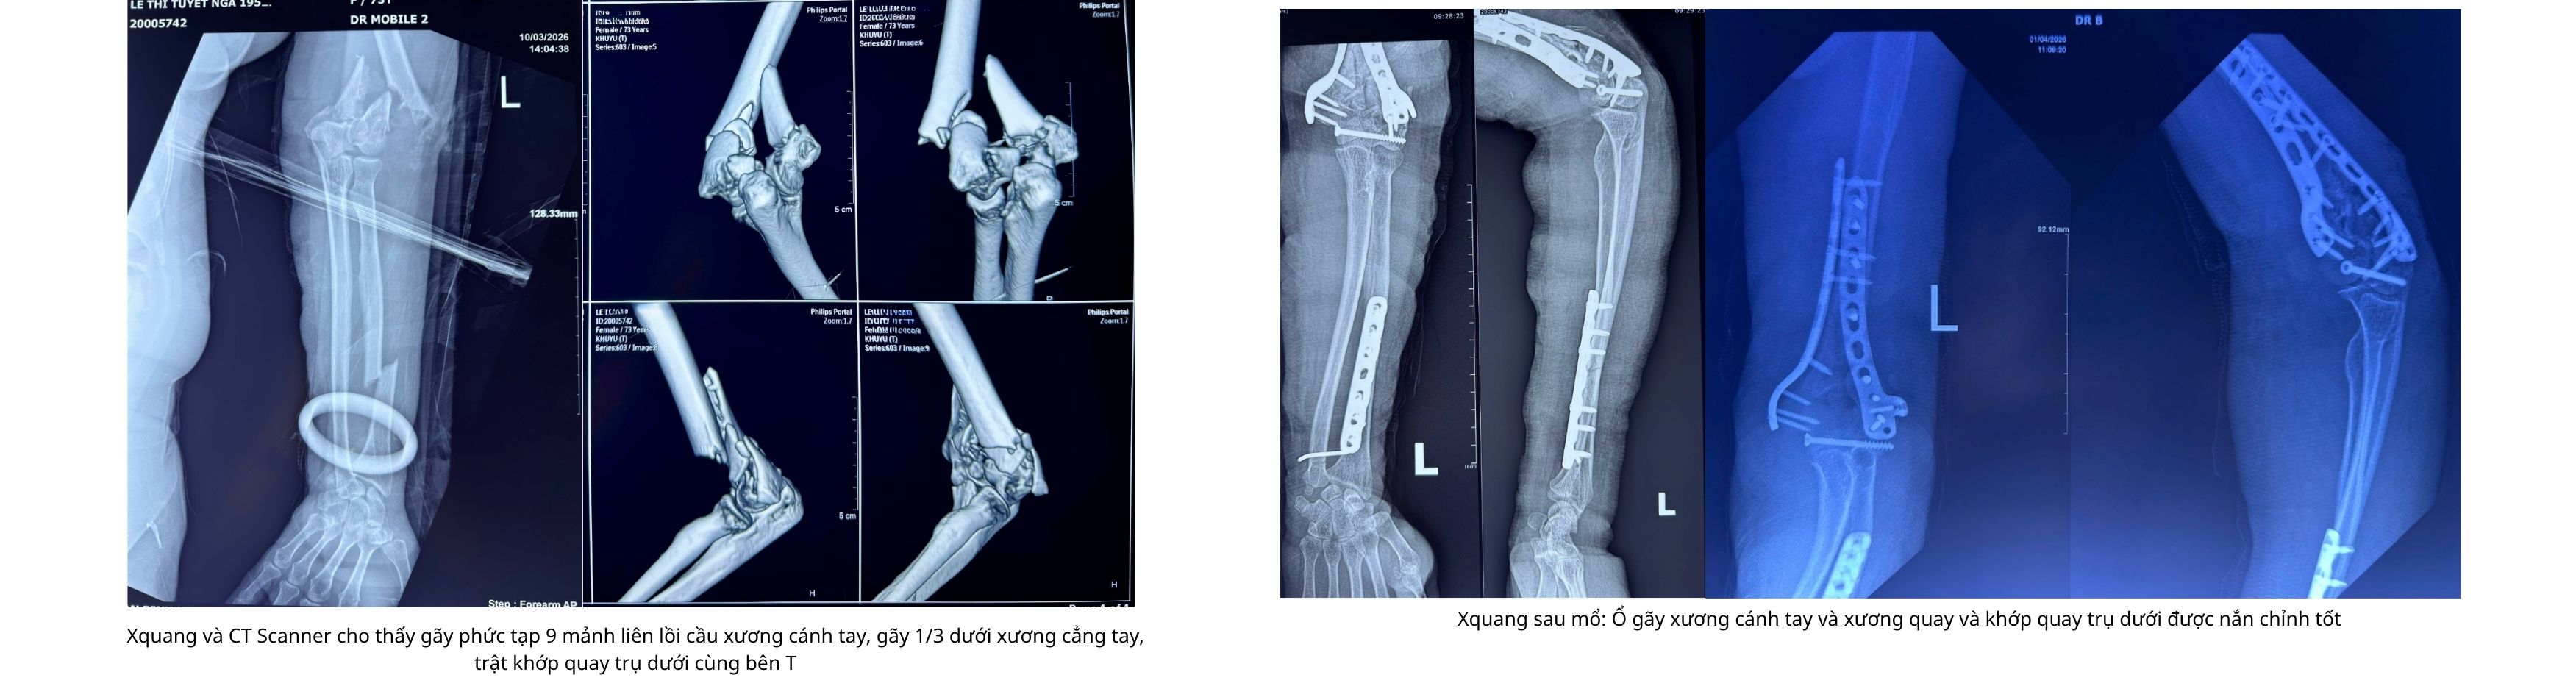

Trường hợp thứ hai là bệnh nhân bị gãy hở độ II nhiều mảnh liên lồi cầu xương cánh tay, kèm gãy 1/3 dưới xương cẳng tay và trật khớp quay trụ dưới, cũng có bệnh lý nền tăng huyết áp, đái tháo đường.

Các bác sĩ lựa chọn phẫu thuật hai thì. Ở thì đầu, bệnh nhân được mổ cấp cứu cắt lọc và cố định tạm để kiểm soát nguy cơ nhiễm trùng. Sau đó, ở thì hai, ê-kíp tiến hành kết hợp xương bằng nẹp vít và cố định khớp bằng kim Kirschner nhằm phục hồi cấu trúc giải phẫu và chức năng vận động.

Kết quả, sau 2 tuần phẫu thuật, vết mổ của cả hai bệnh nhân liền tốt, biên độ vận động khớp khuỷu phục hồi đáng kể.